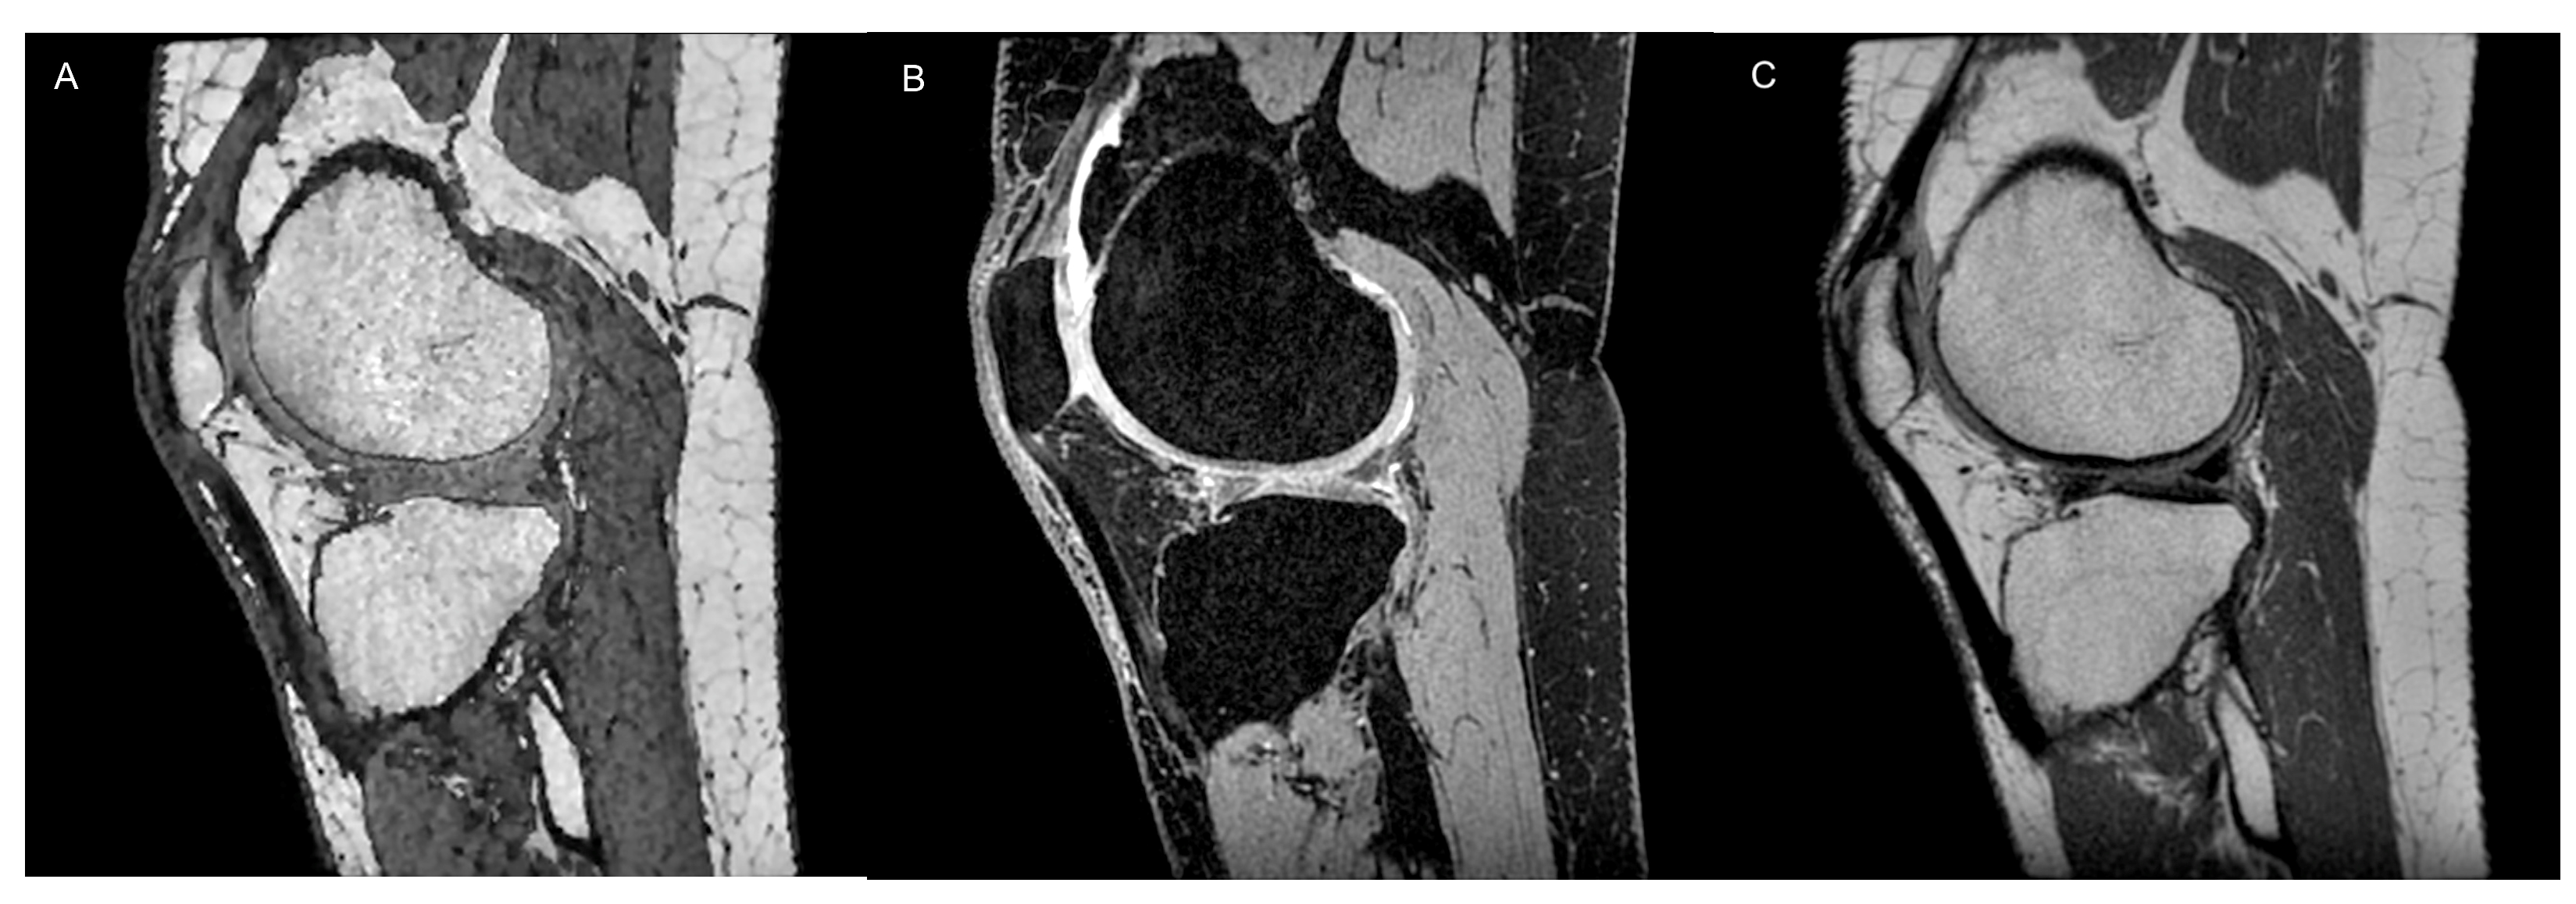

2.2. Cartilage Morphometry

- Graichen, H.; Eisenhart-Rothe, R.V.; Vogl, T.; Englmeier, K.; Eckstein, F. Quantitative assessment of cartilage status in osteoarthritis by quantitative magnetic resonance imaging: Technical validation for use in analysis of cartilage volume and further morphologic parameters. Arthritis Rheum. 2004, 50, 811–816. [Google Scholar] [CrossRef] [PubMed]

- Eckstein, F.; Cicuttini, F.; Raynauld, J.-P.; Waterton, J.; Peterfy, C. Magnetic resonance imaging (MRI) of articular cartilage in knee osteoarthritis (OA): Morphological assessment. Osteoarthr. Cartil. 2006, 14 (Suppl. S1), 46–75. [Google Scholar] [CrossRef] [PubMed]